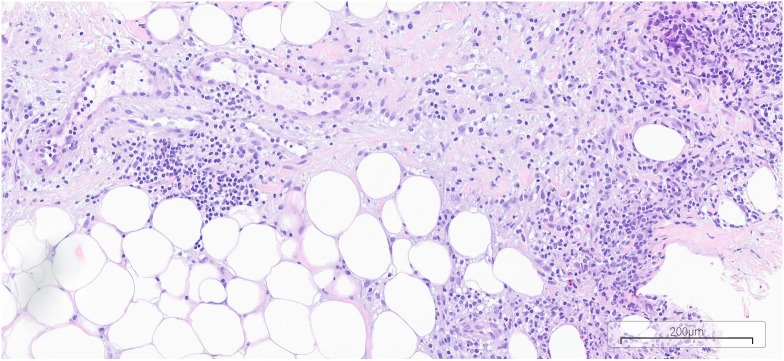

Neutrophil dermatitis is a group of diseases characterized by the leakage of neutrophils in the skin and subcutaneous tissue with a non-infectious, autoinflammatory etiology. These include the aseptic abscess syndrome (AA). Diagnosis is based on histopathological examination and the exclusion of infectious, allergic, and cancer causes. The paper presents the case of a 41-year-old woman with inflammatory spondyloarthropathy (HLA-B27 antigen present), treated with secukinumab, who developed a painful, inflammatory tumor in her right breast. Antibiotic treatment was ineffective, and histopathological exami- nation detected leaching mainly from granulocytes. Infectious and oncological background changes and IgG4+ disease were excluded. After the diagnosis was confirmed, glucocorticoid therapy was started, which brought rapid improvement, but after the dose was reduced, the tumor relapsed. The re-escalation of the steroid dose and the discontinuation of secukinumab coincided with the exacerbation of ankylos- ing spondylitis, which forced the inclusion of upadacitinib, which was effective and well tolerated. Single studies show high efficacy of TNF inhibitors as well as IL-6 or IL-1 blockades in the treatment of AA and sec- ondary prevention in patients with failed steroid therapy. There are no reports of AA cases in the literature during treatment with secukinumab. Treatment with upadacitinib has so far not caused AA recurrence.